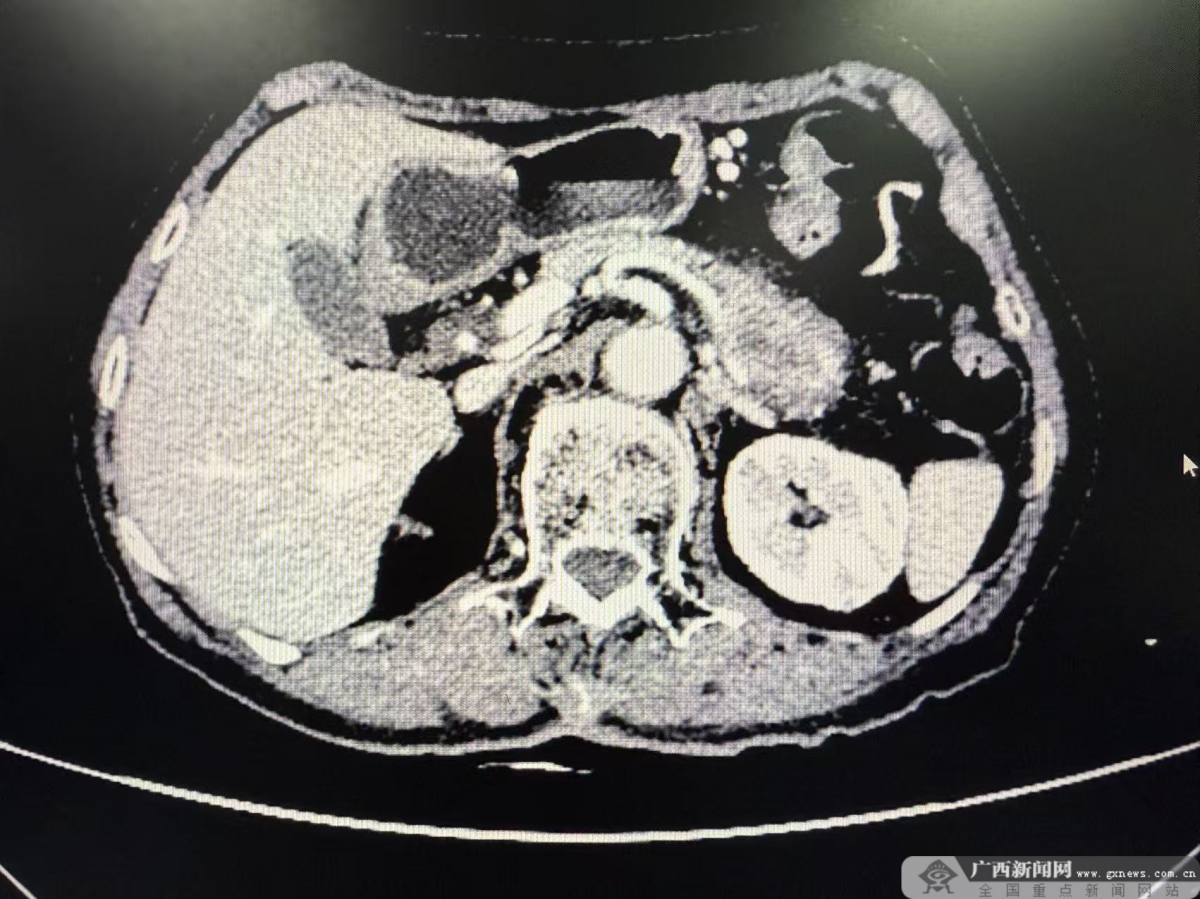

患者CT情况。自治区南溪山医院供图 此前,79岁的吕奶奶被上腹胀痛反复困扰,症状逐渐加重后,她在家人陪伴下来到自治区南溪山医院就诊。其CT检查结果让显示:胰腺体尾部占位4.5cmx3.7cm,考虑恶性肿瘤,从图像上看,肿瘤已侵犯脾动静脉。据悉,胰体尾癌的传统手术方式是胰体尾部加脾脏切除,但是该患者肿瘤已经侵犯脾动静脉,使用传统手术方式容易出现肿瘤残留而无法做到真正的完全切除。而L-RAMPS的手术难度要大于传统手术方式,但是能进行更深层面切除,以期提高患者生存率。